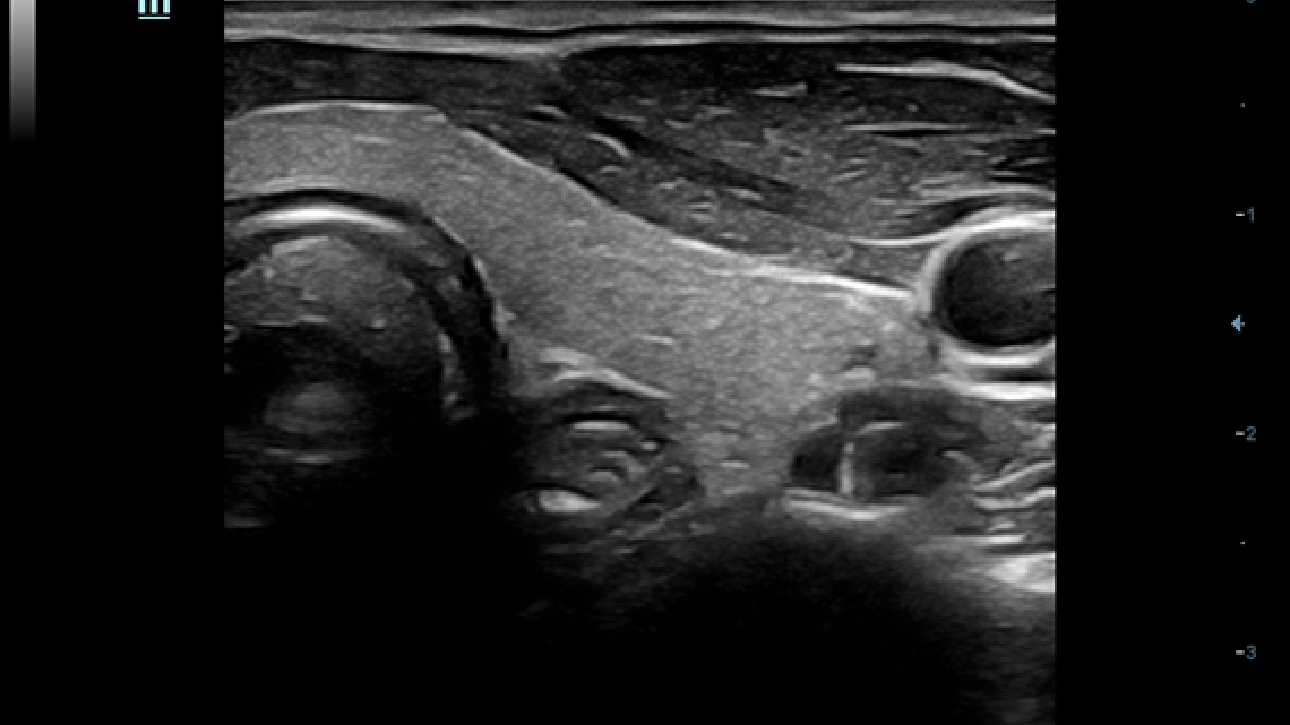

X-Insight, daha geli?mi? g?rĂŒntĂŒler elde etmek i?in kapsaml? bir ??zĂŒmdĂŒr.

Mindrayâin yeni ??zĂŒmĂŒ, geli?en en yeni ultrason teknolojileri ile birlikte, mĂŒ?terilerin g?rĂŒ?lerini klinik gerekliliklerle tam anlam?yla birle?tiren bir ??zĂŒmdĂŒr. Taptaze bir ruhla, gelece?e odaklanarak ve s?n?rs?zl???n pe?inde ko?arak, artan ?l?eklenebilirlikte sĂŒrekli olarak geli?en bir ??zĂŒmdĂŒr.

?ok y?nlĂŒ bir partner olarak, X-Insight'l? DC-60 Exp, her y?nĂŒyle gĂŒnlĂŒk klinik uygulamay? kolayl?kla ve belirsizlik olmadan y?netmenize yard?mc? olacak kapsaml? bir ??zĂŒm sunar.

MĂŒ?teri gereksinimlerine y?nelik g?rĂŒ?ler temelinde, X-Insight'l? DC-60 Exp, eXpress Clarity, eXceptional Intelligence ve eXceeding Experience ile gĂŒ?lendirilerek, hassas g?rĂŒntĂŒlemeyle yĂŒksek verimlilik sa?layacak ?ekilde tasarlanm??t?r.